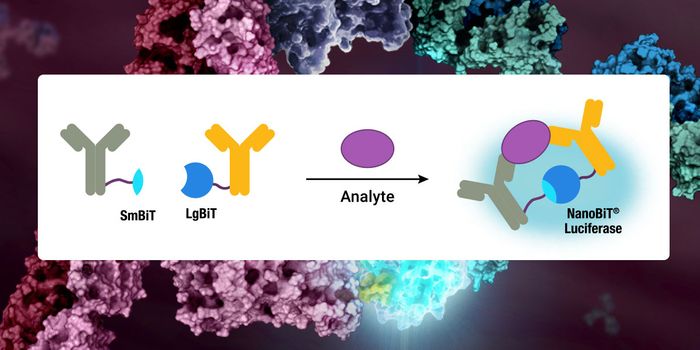

JUN 29, 2021ImmunologyAmid the widespread outbreak of the COVID-19 caused by SARS-CoV-2, the development of test methods that can efficiently ...